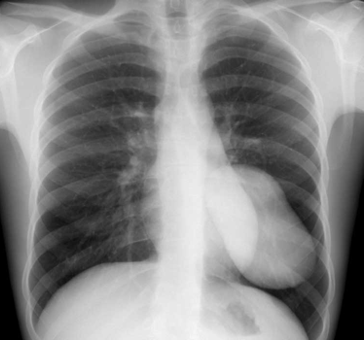

Rx toracică, incidență P-A

DESCRIERE:

la niv. întregului hemitorace drept → opacitate extinsă, nesistematizată, de intensitate mare, omogenă

caracter expansiv → împinge traheea și mediastinul de partea opusă

diafragm deplasat în jos

lărgirea spațiilor intercostale

umplerea spațiului costo-diafragmatic

DX: pleurezie masivă

DD: atelectazie → caracter retractil